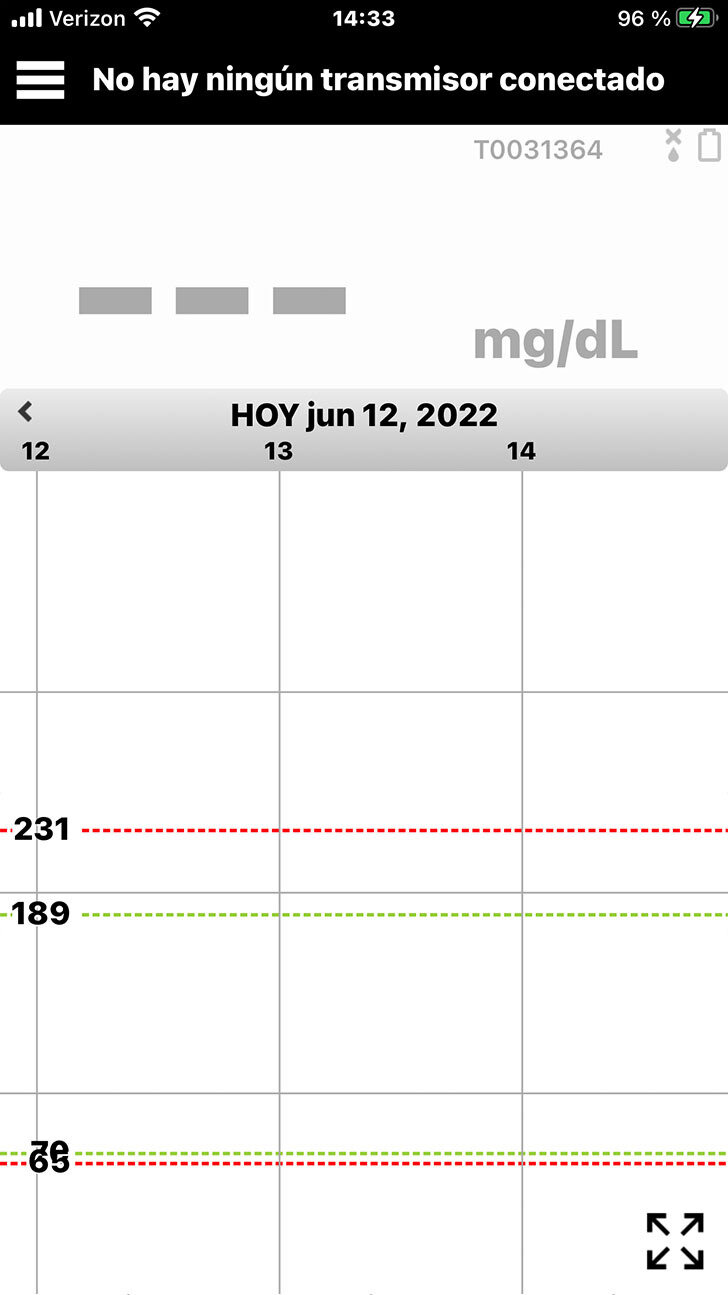

Si no está conectado, el icono

de la batería estará gris y la barra

de estado de la aplicación indicará No hay ningún transmisor conectado.

Si aparece la indicación No hay ningún transmisor conectado |